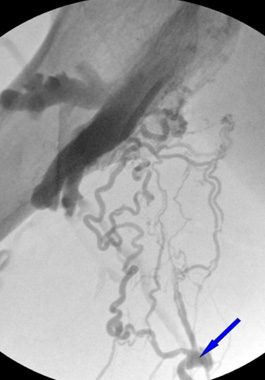

大きな血管だけを対象に細静脈下肢静脈瘤の原因を探す検査方式

足には無数の静脈があり、大きく深部静脈、伏在静脈、細静脈などに区分できます。

伏在静脈は、大伏在静脈と小伏在静脈に分けられます。大伏在静脈は鼠径部に始まり内くるぶしへと続く静脈で、小伏在静脈は膝窩(膝の裏側)から外くるぶしへと続く静脈を指します。

伏在静脈は足の静脈の中でも主要の静脈で、大きな静脈の一つです。そのため、多くの病院では伏在静脈のみを検査し治療します。